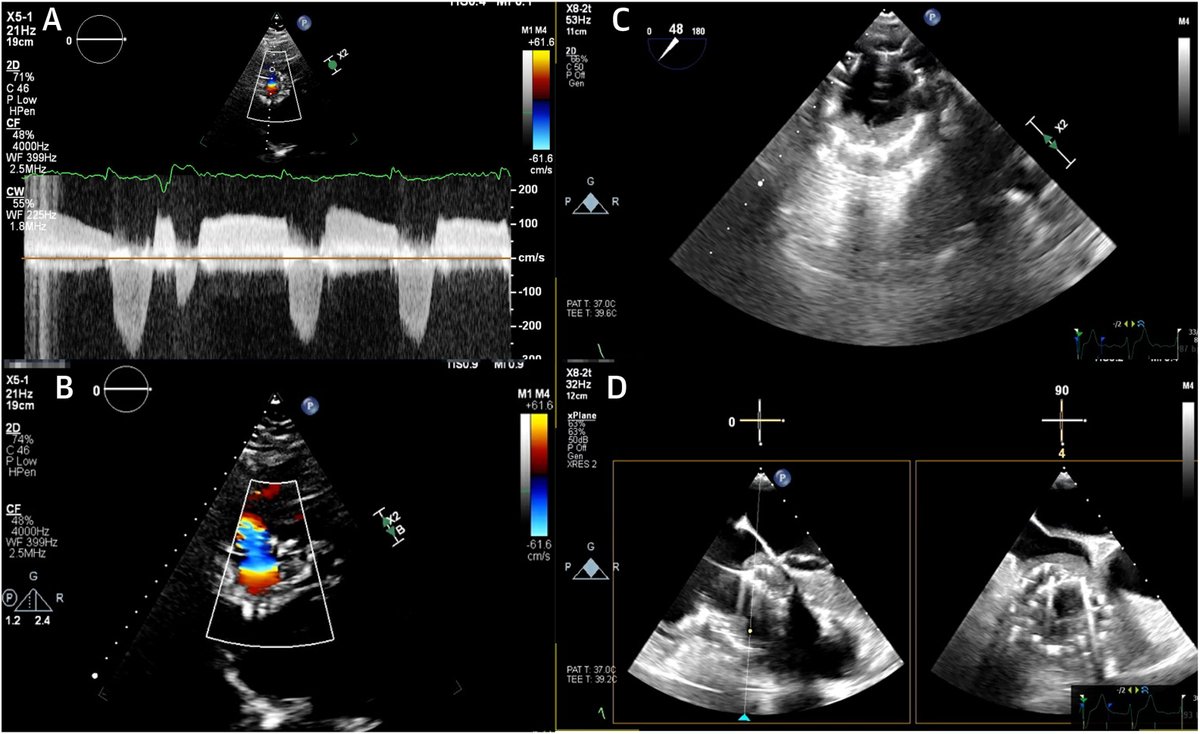

FANTASTIC MUST-READ #JACCIMG @JACCJournals SOTA review on Post #Evoque #TTVR Echo #TTE imaging. Comprehensive, practical! Download full paper here FREE for a LIMITED TIME! https://t.co/lfhJ0khJAw https://t.co/DgyCXnMOOF